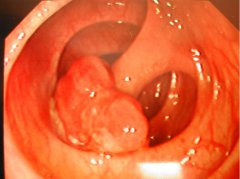

腸息肉是指腸黏膜表面突出的異常生長的組織,在沒有確定病理性質前統(tǒng)稱為息肉。其發(fā)生率隨年齡增加而上升,男性多見。以結腸和直腸息肉為最多,小腸息肉較少。息肉主要分為是炎癥性和...